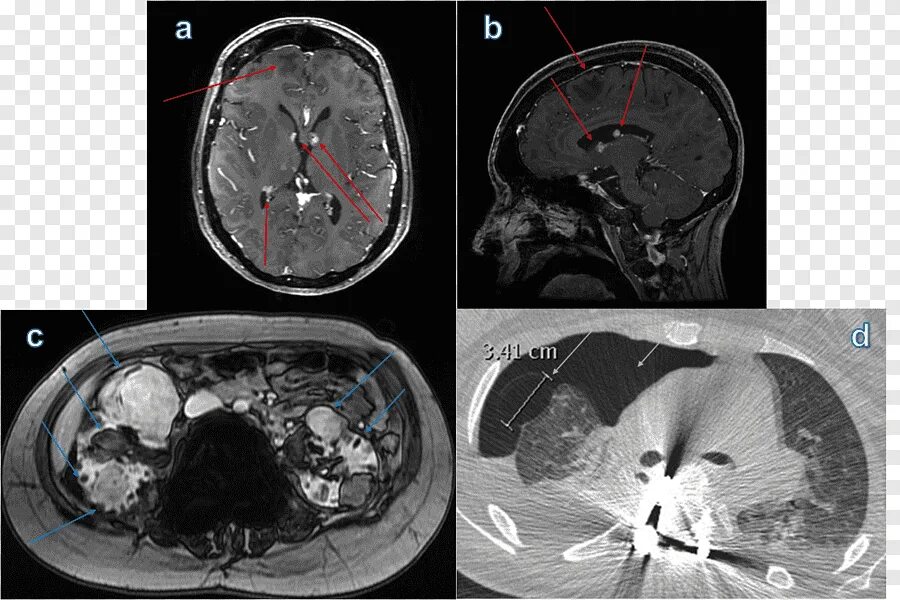

Плохо после контраста кт